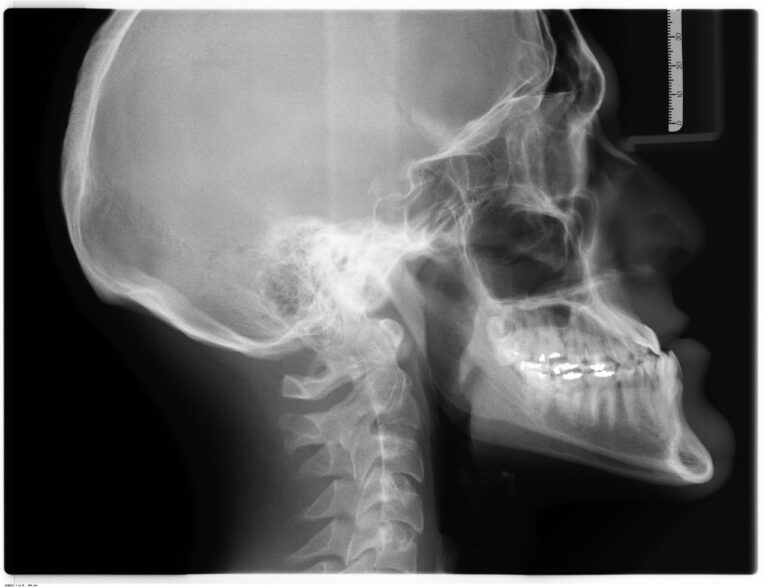

Leczenie kanałowe jest jedną z najczęściej wykonywanych procedur w gabinetach stomatologicznych. Procedura ta polega na usunięciu zakażonej lub uszkodzonej miazgi z wnętrza zęba, a następnie wypełnieniu powstałej przestrzeni specjalnym materiałem. Leczenie kanałowe pozwala uratować ząb, który w przeciwnym razie musiałby…